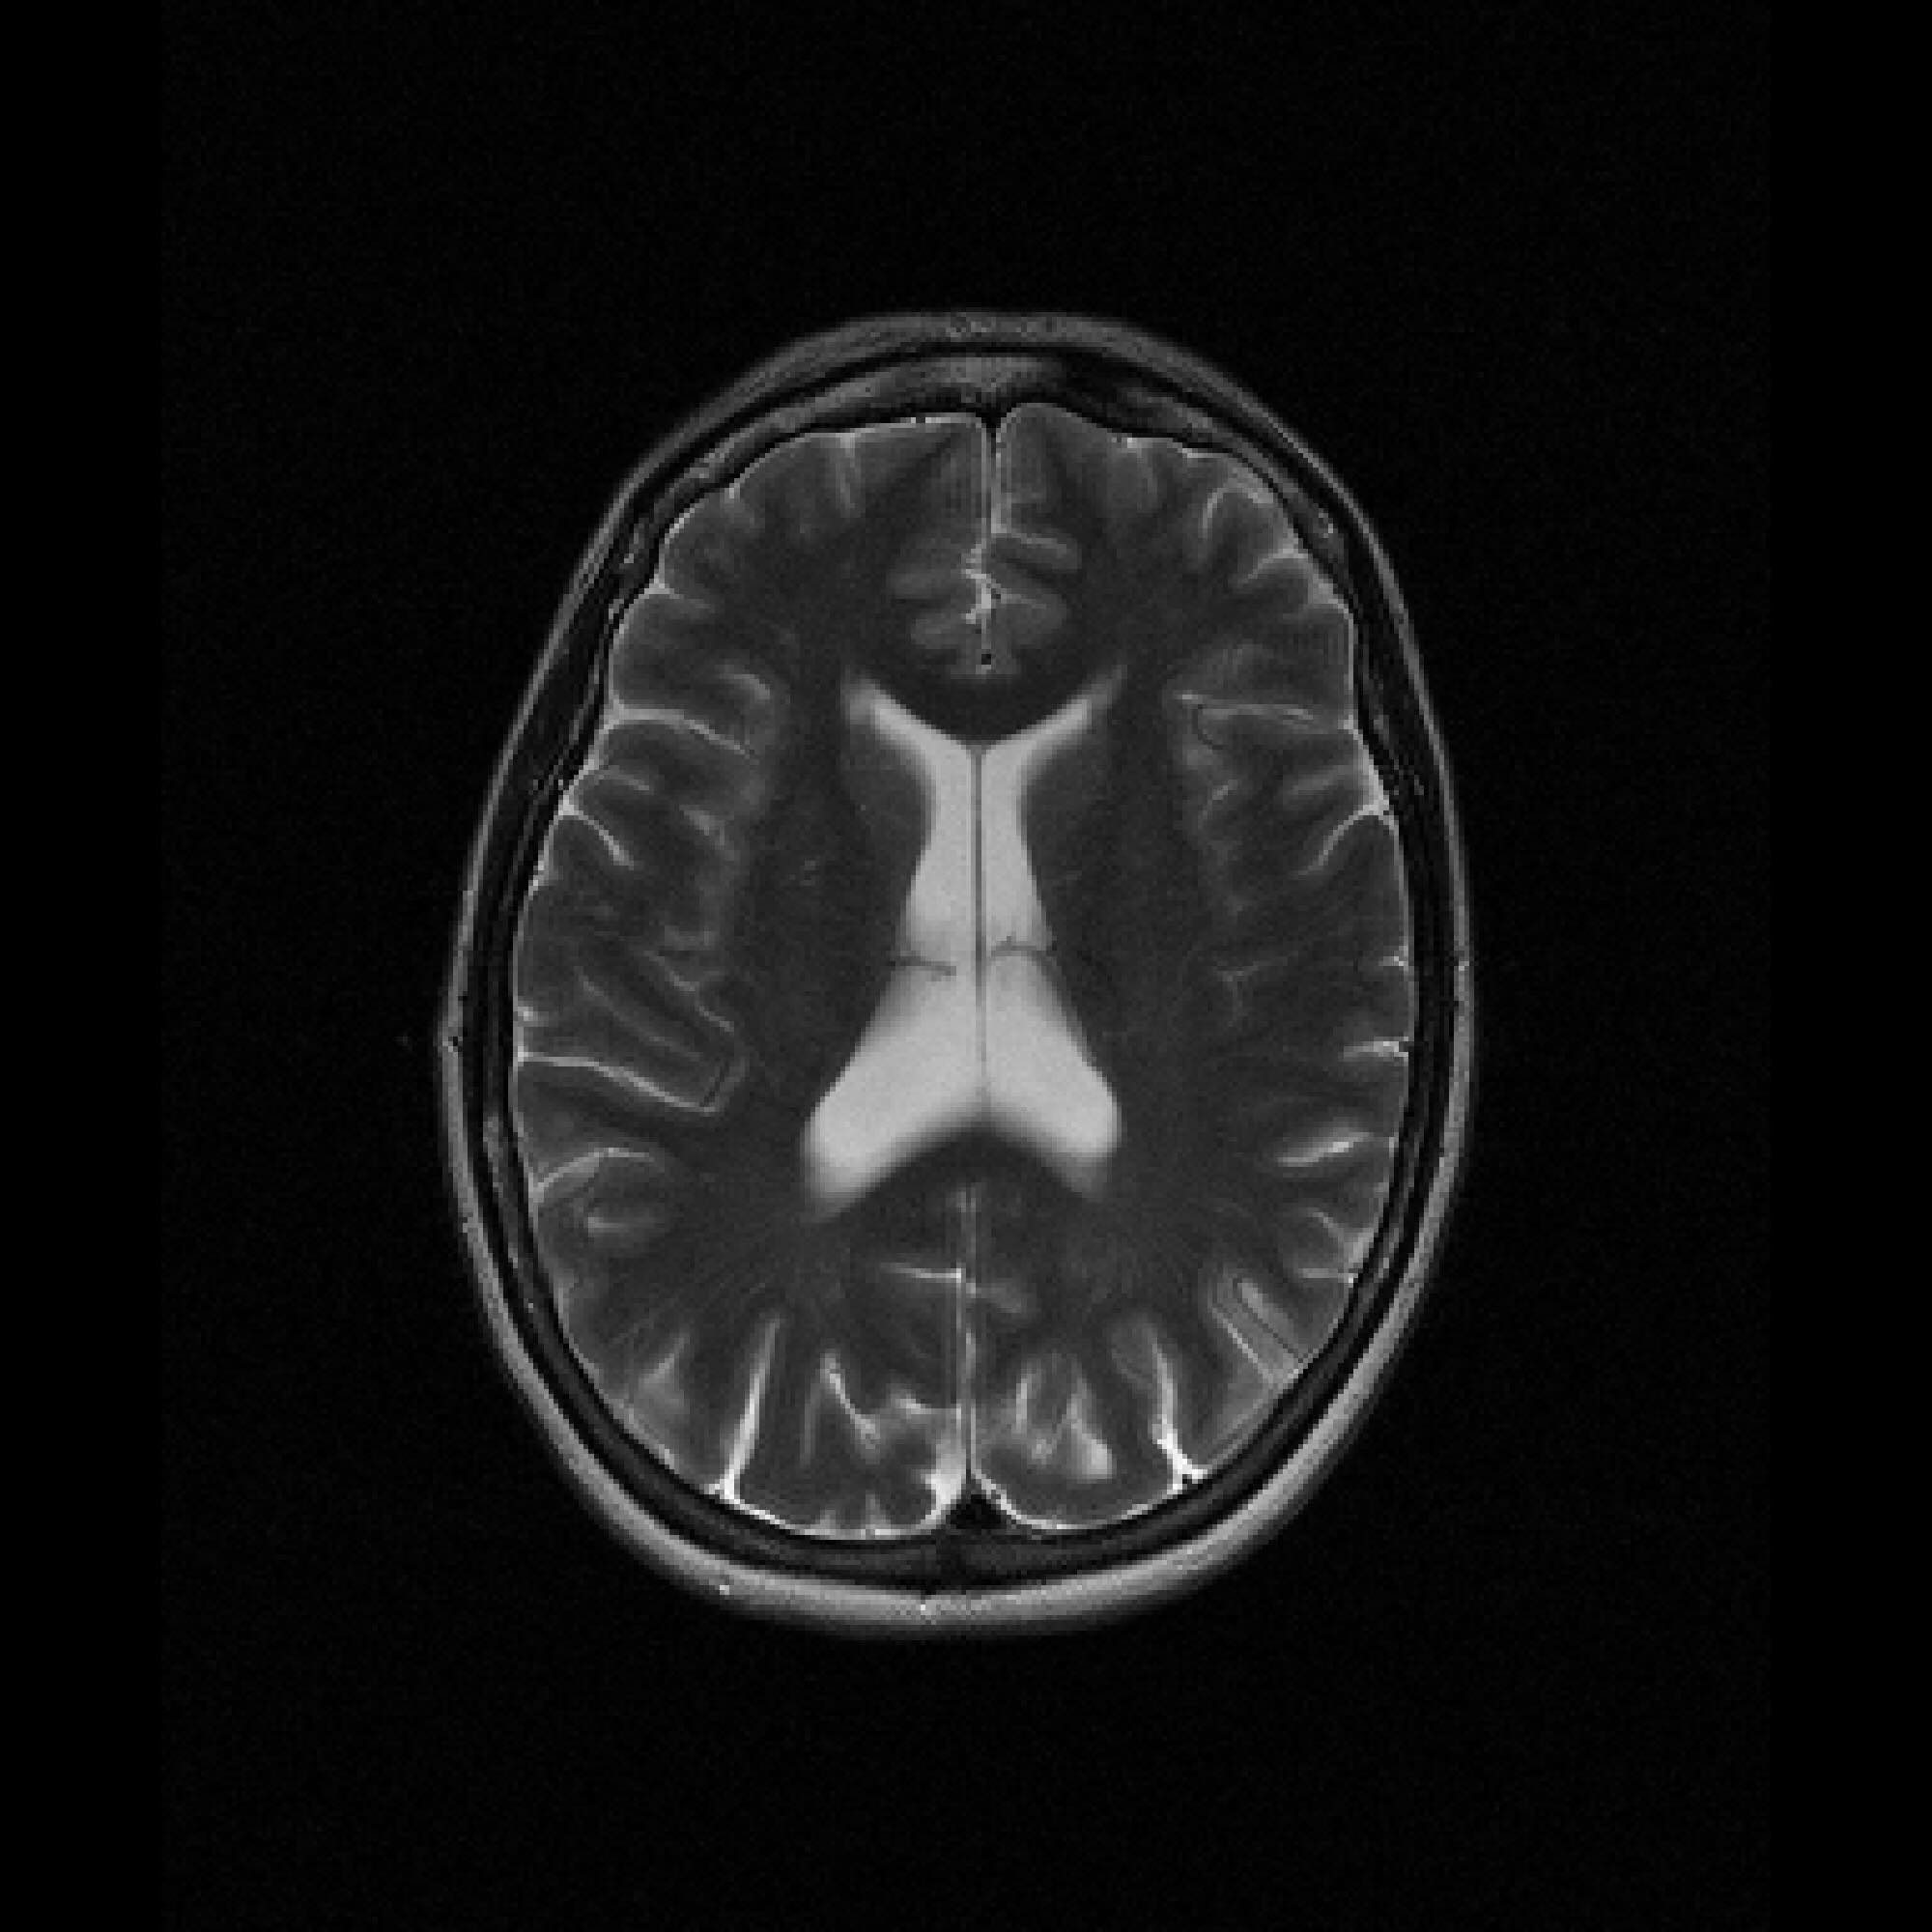

Figure 2: Example MRI magnitude reconstructions with S=25S=25 training slices at acceleration factor R=7R=7. PaDIS-MRI reconstructions are sharper and more faithful to the fully-sampled ground truth. Insets are shown to highlight detail.

Figure 2 provides a visual comparison of the reconstruction quality of each method on example slices. In reconstructions from the S=25,R=7S=25,R=7 models, FastMRI-EDM exhibits slightly more blurring and loss of fine structural details, particularly in regions with complex anatomical features. PaDIS-MRI, in contrast, preserves sharper boundaries and finer details. This enhanced data efficiency can be attributed to the patch-based prior’s ability to learn localized structural motifs more effectively from limited examples. Figure 6 in the Appendix shows similar reconstructions at S=200,R=7S=200,R=7 where FastMRI-EDM more closely approaches the performance of PaDIS-MRI but still struggles with highly detailed anatomy. At both dataset sizes, MoDL underperforms the diffusion priors. In Figure 2, MoDL’s FLAIR reconstruction exhibits pronounced artifacts, likely reflecting reduced generalizability of a supervised prior when the training distribution underrepresents FLAIR.